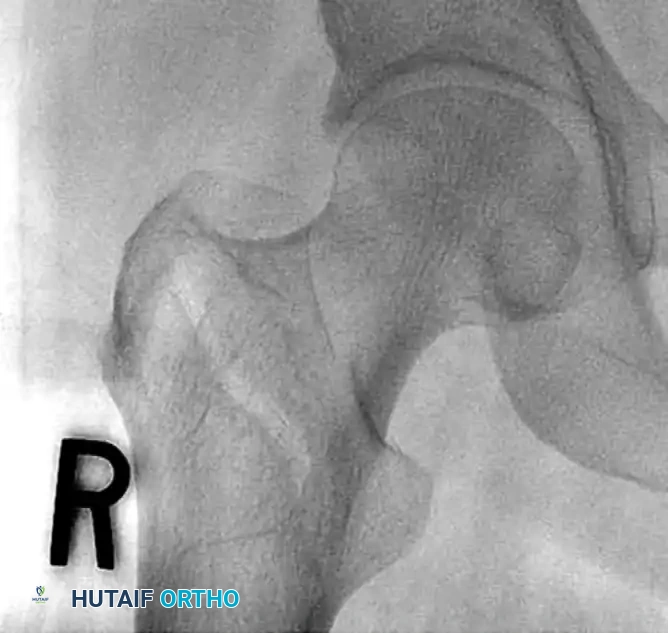

CLOSED REDUCTION MANEUVERS

Surgical Warning: Never proceed with the surgical incision until an acceptable closed reduction is confirmed on both AP and lateral fluoroscopic views. A poorly reduced fracture cannot be salvaged by a perfectly placed implant.

- Standard Reduction: Reduction of the affected extremity is typically achieved through longitudinal traction followed by internal rotation. The internal rotation corrects the external rotation deformity caused by the short external rotators and gravity, bringing the femoral neck parallel to the floor.

- Correcting Sagittal Deformity: The most common sagittal plane deformity is a posterior sag of the fracture site. This may require correction via an anteriorly applied force (e.g., a crutch or a specialized reduction tool placed under the posterior thigh) to lift the distal fragment before finalizing the reduction with traction and internal rotation.

- Fluoroscopic Scrutiny: Carefully scrutinize the images to rule out varus deformity, posterior sag, and excessive internal rotation. A slight valgus reduction is biomechanically superior to any degree of varus.